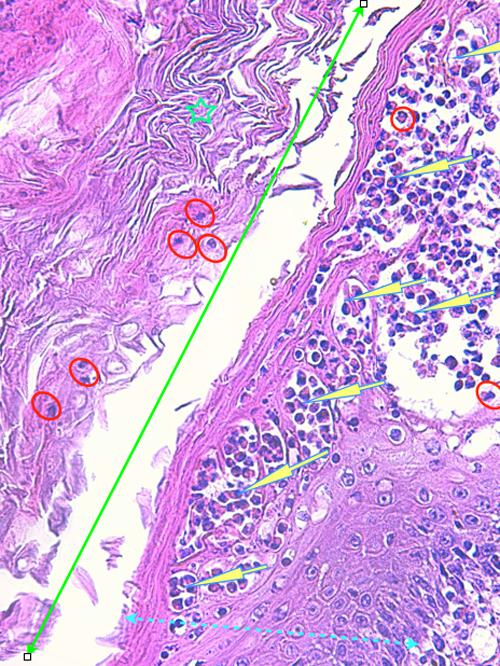

Photo 2 (Hémalun Eosine X 100) peau velue : Vue rapprochée de la Photo 1,

sur un infundibulum folliculaire criblé de pustules pariétales microloculaires.

On note une hyperkératose orthokératosique de l’infundibulum adjacent.

Légendes de la Photo 2 :

- Double flèche bleue pointillée : grand axe des infundibula folliculaires

- Double flèche verte : derme

- Étoiles rouges pleines : erreur (!)

- Ovales jaunes : pustules folliculaires pariétales (folliculite murale)

- Étoiles vertes évidées : lumière des follicules pileux, à gauche parakératosique, à droite orthokératosique

Photo 5 (Hémalun-Eosine X100) peau velue : Les infundibula folliculaires peuvent contenir

dans leur lumière, obstruée de kératine, des granulocytes, mais c’est surtout leur gaine épithéliale

externe qui est le siège de micro-pustules multiloculaires.

Légendes de la Photo 5 :

- Double flèche verte : lumière de l’infundibulum folliculaire

- Étoiles turquoises : infiltrat inflammatoire dermique périannexiel

- Étoile verte : kératine intra-folliculaire

- Ronds rouges : pustules folliculaires luminales et parétales (folliculite murale et luminale)